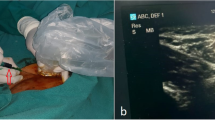

ICG is available as a 25-mg powder (Aurogreen; Aurolabs, Madurai, India) and is reconstituted in 10 ml of water, with each ml of the solution containing 2.5 mg of dye. ICG is injected in the inguinal nodes bilaterally (each side 1 ml, total 5 mg) under sonographic guidance before the start of surgery at the time of induction of anesthesia. For the last 6 months, we have been injecting ICG just before thoracoscopy.

To perform ICG lymphography, we selected inguinal lymph nodes as they are superficial, easily accessible, consistently present, and relatively larger in size and easy to visualize under ultrasound.

We systematically conduct sonographic evaluation of the inguinal region, specifically the femoral triangle, with the patient in a supine position and the thigh slightly abducted. It is crucial to have a deep understanding of the region’s anatomy. The lymph nodes are positioned superficially to the fascia lata. A typical lymph node exhibits an oval shape, regular contours, a hilum with blood flow, and a central hyper-echogenic medulla surrounded by a thin and uniformly hypo-echogenic cortex. A successful injection is indicated by the enlargement of the nodal size, and the central hyper-echogenic medulla loses its normal echotexture, becoming hypoechoic.

Studies by Ashitate et al. [20] and Steffey and Mayhew [21] have reported real-time imaging of TD anatomy in animal models using NIR fluorescence imaging with ICG. Numerous case reports and series have successfully identified the TD by injecting ICG into subcutaneous tissue, mesentery, dorsum of the foot, and intranodally [11,12,13,14,15,16,17, 19, 22]. However, intranodal injection has shown the most consistent TD visualization, even after repeat and failed surgeries [6]. Ultrasound-guided inguinal node injection is a safe and feasible method to obtain TD visualization, especially for real-time lymphography [6, 10, 19]. In our series, six patients did not show TD. These cases occurred during the initial phase of implementing the technique at our institute. This approach is safe and easy to learn, but we want to be self-critical and believe in these cases the dye was not successfully injected into the nodes. In most cases, clear and fast visualization was possible with NIR-ICG, as demonstrated in 93% of our series.

We observed that the key to successful imaging of the TD is proper ultrasonographic identification of the inguinal node, image-confirmed intranodal ICG injection with node expansion, and loss of central hypoechoic region. An advantage of intranodal injection is that it provides a constant supply of ICG for fluorescence, lasting for the entire duration of surgery, enabling real-time fluorescence surgery. Our experience suggests that ultrasound-guided intranodal injection is easy to perform, fast (5–10 min), and can be performed by surgeons themselves. In six cases, we encountered difficulties visualizing the duct because the dye had not been properly injected into the nodes. Once the dye is within the nodes, it consistently remains within the lymphatic system and, consequently, within the TD. The absence of TD visibility implies that the dye was likely injected outside the node, a common occurrence, especially when administered by someone inexperienced or in early phase of learning.